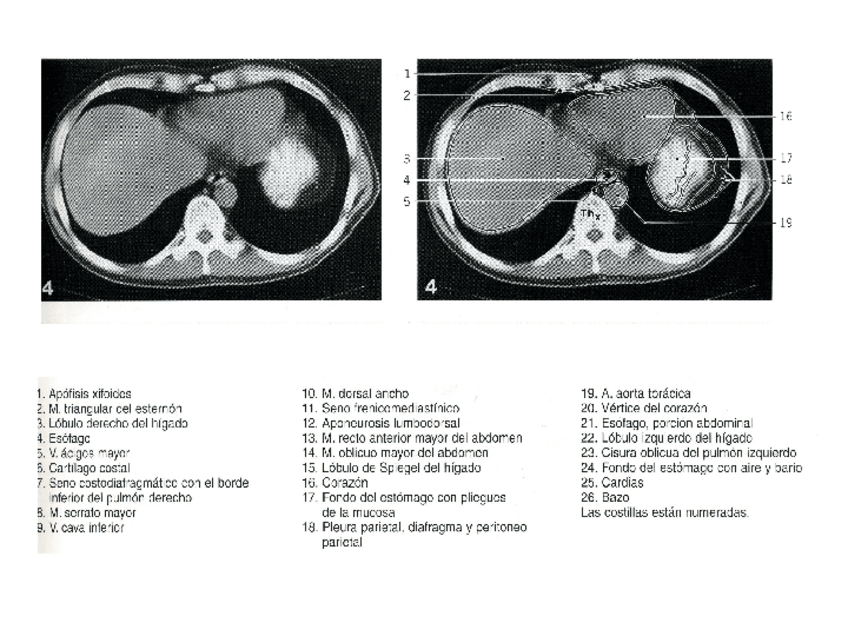

He publicado nuevos apuntes de Técnicas de Tomografía Computarizada y Ecografía: ABDOMEN.ppt

powerpoint